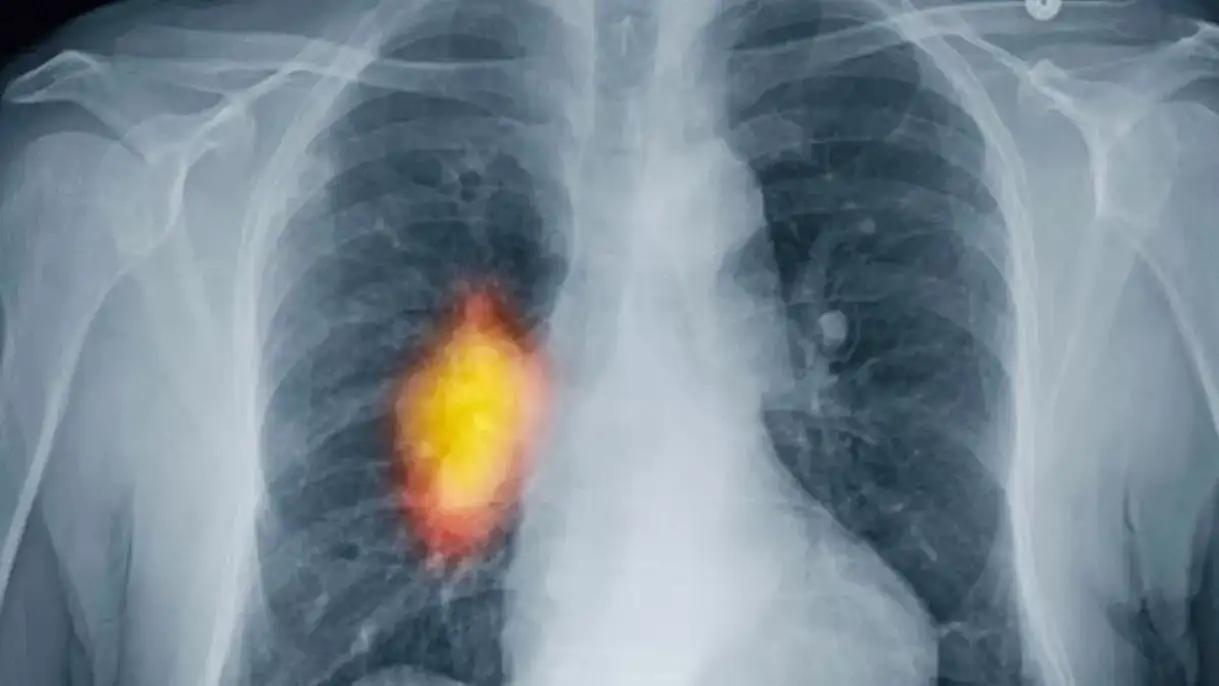

“Akciğer kanseri en çok ölüme neden olan kanser türü”

Günümüzde eskiye kıyasla daha fazla kanser görülmesi nedeniyle bunun bir halk sağlığı sorunu kabul edilerek bazı tümör türlerinde tarama programları oluşturulduğuna dikkat çeken Doç. Dr. Karakaş “Son verilere göre yılda 19.3 milyon yeni kanser vakası tespit edilmiş ve 10 milyon kişi de ne yazık ki hayatını kaybetmiştir. Hem erkek, hem de kadınlar birlikte değerlendirildiğinde akciğer kanseri en sık görülen ve en çok ölüme neden olan kanser türüdür. Erkeklerde bunu prostat ve kolorektal (bağırsak) kanserleri izler. Kadınlarda ise en sık ve ölümcül olan meme kanseridir. Kadınlarda meme kanserini, akciğer ve kolorektal (bağırsak) kanseri takip eder” dedi.